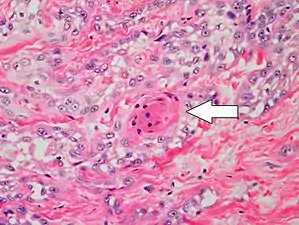

Poorly differentiated, where attempts at keratinization are often no longer evident. This is a clear-cell squamous-cell carcinoma. The dysplastic cells infiltrated cords through the dermis. Poorly differentiated cSCC has greatly enlarged pleomorphic nuclei showing a high degree of atypia and frequent mitoses.[12]

Poorly differentiated clear-cell squamous-cell carcinoma. For this type of cSCC, immunostains will likely be required to classify it unless other areas of the tumor show obvious squamous-cell features such as seen here (arrow).